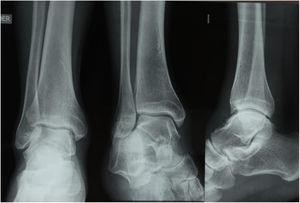

En el caso 3 se estableció como criterio quirúrgico 1mm de discrepancia de la línea de shenton y una apertura de el espacio claro medial de 6mm, además de una malrotacion del peroné y discrepancia de el ángulo talocrural, como se observo en las figuras 6 y 7. figura 8, figura 9